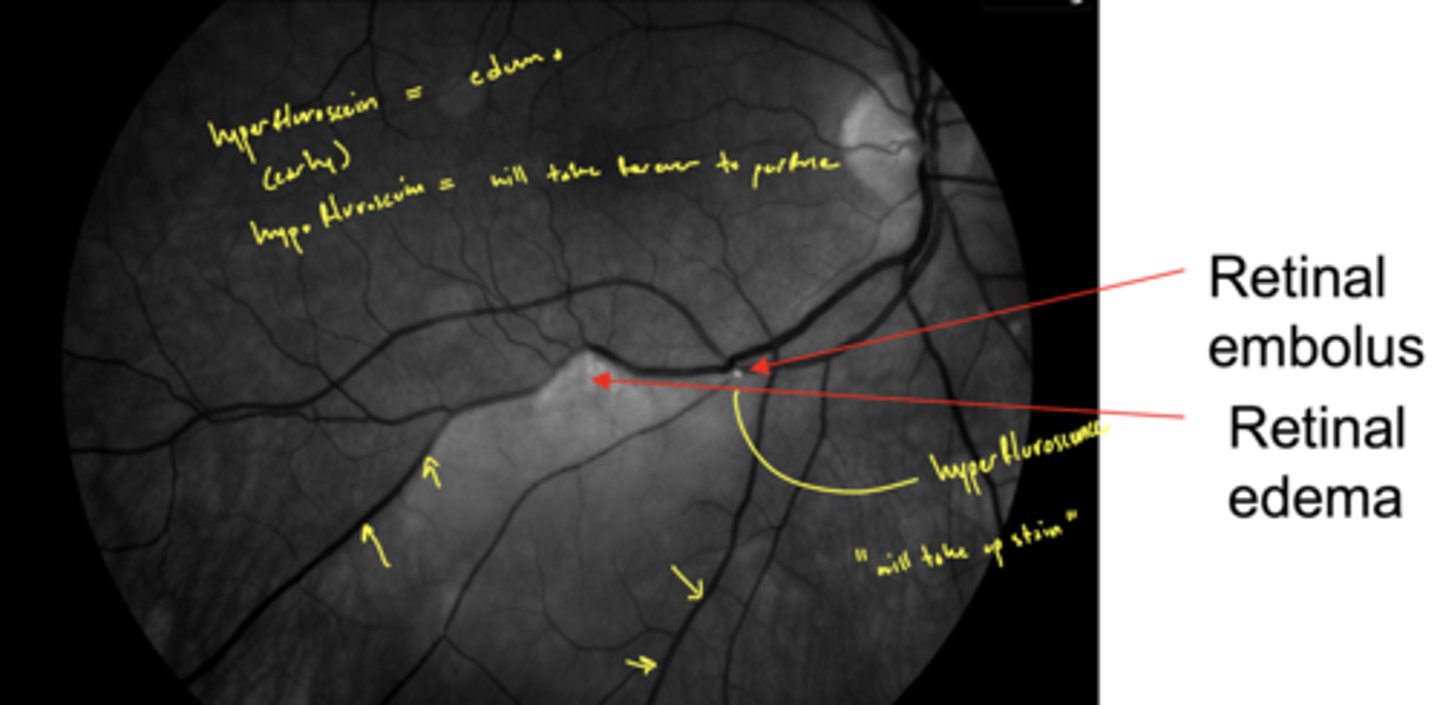

What causes a BRAO?

emboli dislodged from vasculature elsewhere in body; typically the heart or the carotids

What symptom is BRAO often associated with?

amaurosis fugax (transient monocular blindness)

Why are BRAO an emergency?

rapid anoxia of inner retina

cause anoxia that causes loss of inner retinal layers (NFL, GCL, IPL, INL) - retinal tissue changes from hazy to white in a few hours

image would be considered hemicentral technically

What does a BRAO look like on FANG?

hyperfluorescence (from edema) early on as occluded blood vessel leaks

then eventually hypofluorescence